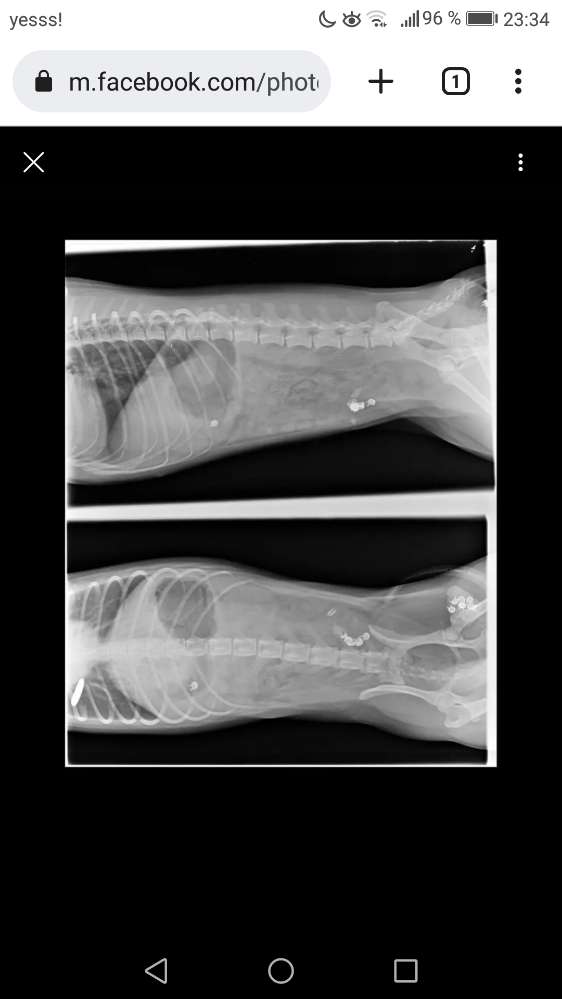

Ein Hund musste heute mit

Vergiftungserscheinungen zum Tierarzt.

Es wurden kleine Metall Kugeln im Kot gefunden!